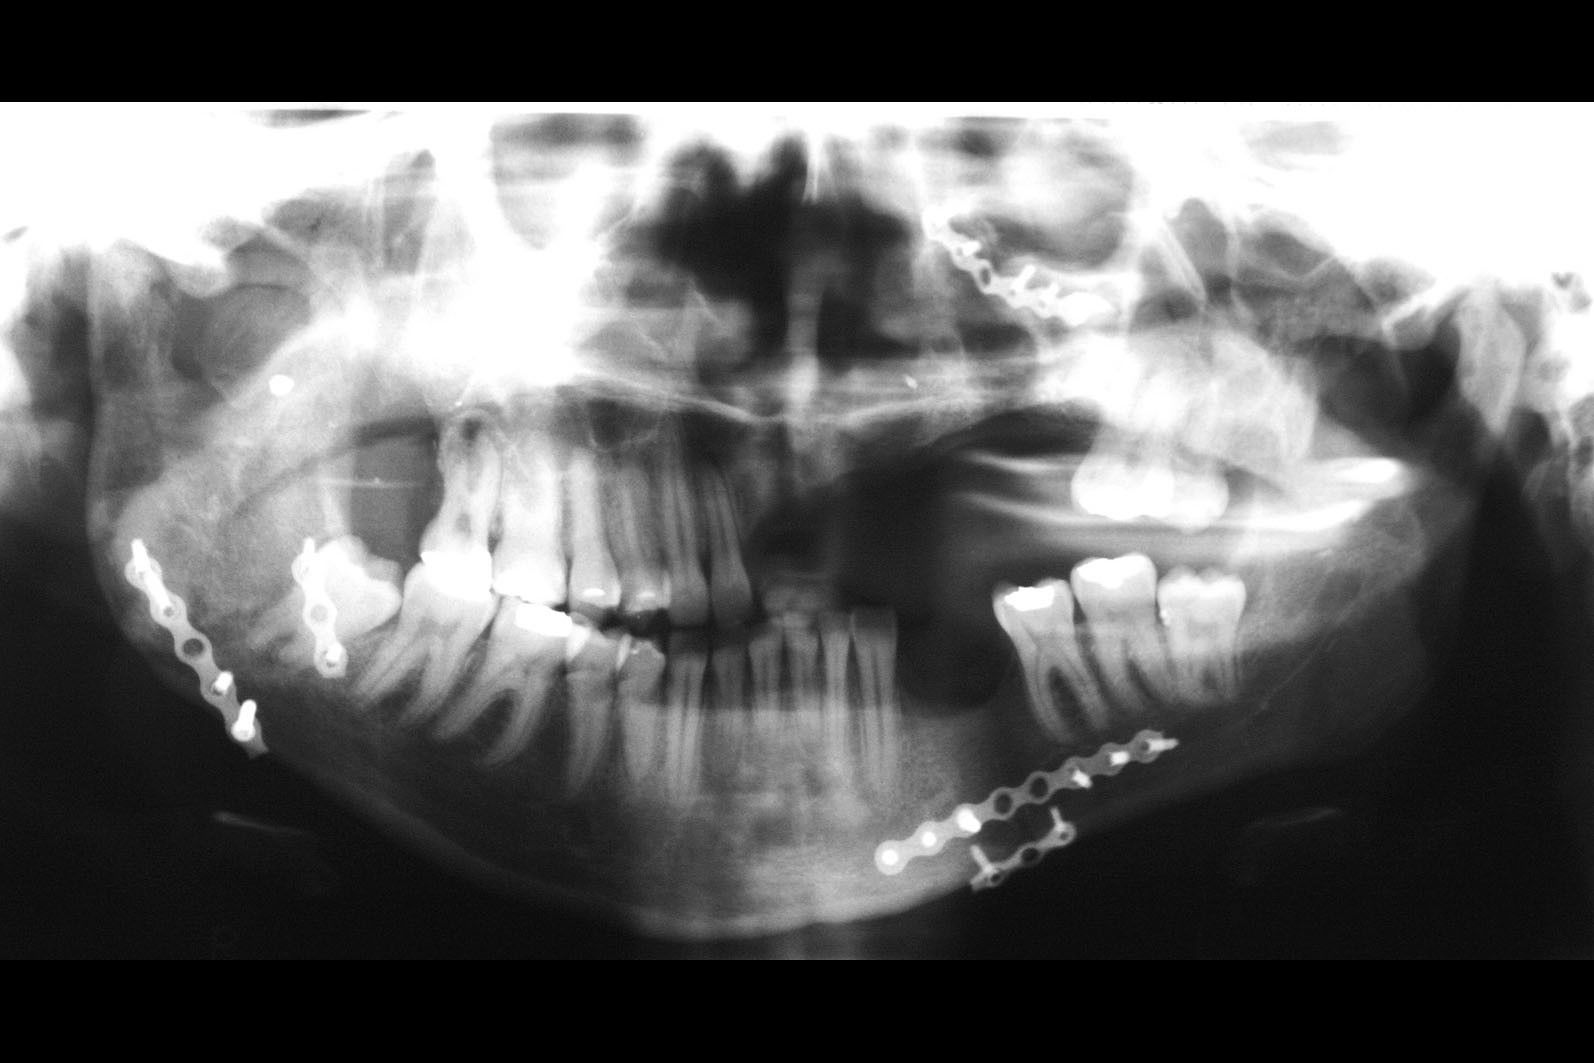

W ocenie wewnątrzstawowych patologii pomocna jest diagnostyka obrazowa. Konwencjonalne zdjęcia radiologiczne OPG, tomografia komputerowa oraz stożkowa tomografia komputerowa CBCT pozwalają na ocenę elementów kostnych stawu skroniowo-żuchwowego. Ocenę tkanek miękkich zlokalizowanych wewnątrzstawowo umożliwia rezonans magnetyczny NMR.

W pierwszym etapie wykonuje się modele robocze, które są montowane w opracowanym przez prof. Gerbera artykulatorze. Tak zwany condylator pozwala na symulację trójwymiarowych ruchów głów żuchwy. Pozwala na zweryfikowanie poprawności relacji pomiędzy łukiem zębowym górnym a dolnym. Po dokładnym zbadaniu funkcji i morfologii stawu sż, wykonaniu pomiarów oraz ocenie stanu zdrowia zębów zostaje opracowany indywidualny plan leczenia zgodny z uwarunkowaniami pacjenta.

Utratę każdego zęba należy uzupełnić możliwie jak najszybciej, ponieważ nawet pojedyncze braki zębowe mogą prowadzić do niekorzystnych następstw dla całego układu żucia. Po utracie zęba dochodzi do zaniku kości wyrostka zębodołowego w wyniku braku jej osiowego obciążenia siłami żucia. Dochodzi do przemieszczania się zębów pozostałych w sąsiedztwo powstałej luki. Mogą się one przechylać, obracać i wysuwać z zębodołu bez względu na to, czy dotyczy to łuku górnego czy dolnego. Ruchy zębowe uzasadnia ich fizjologiczne dążenie do kontaktu ze sobą. Stąd braki zębowe w przeciwstawnym łuku deformują zgryz. Proces ten opisywany jest jako objaw Godona.

W rezultacie prowadzi to do utraty kolejnych zębów. Następstwa postępujących braków zębowych prowadzą do powstania zaburzeń funkcji stawów skroniowo-żuchwowych. Mogą objawiać się trudnościami w rozwieraniu szczęk, bólami mięśni twarzy i głowy w okolicach skroni, jak również prowadzić do zaburzeń trawiennych. Poza funkcją istotna jest również estetyka. Widoczne w uśmiechu braki zębowe, skrócenie dolnego odcinka twarzy, zapadnięcie się warg czy tworzenie się zmarszczek w okolicy ust to tylko niektóre z następstw towarzyszących ubytkom uzębienia. Uzupełnianie braków zębowych przywraca podstawy fizjologii jamy ustnej, ponieważ zęby jako zespół funkcjonują prawidłowo tylko w komplecie.